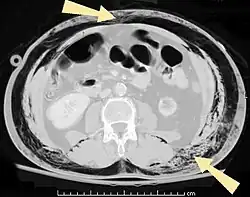

Bubbles of air in the subcutaneous tissue (arrow) feel like mobile nodules that move around easily.